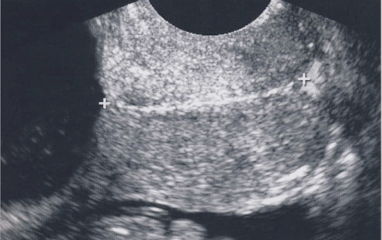

SONO: cervical cerclage

post-cerclage procedure; imaged transvaginally

cerclage stitches are echogenic with posterior shadowing

serial scans may be done to ensure cerclage remains secure and cervix is closed

what are the arrows pointing to?

cervical cerclage stitches